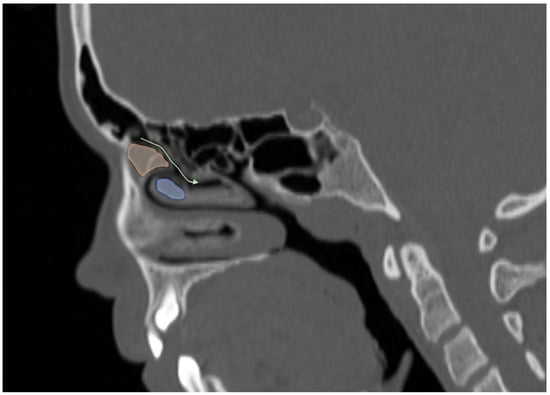

Figure 4.

Sagittal reformatted CT image of a 14-year-old girl showing Agger Nasi cell (orange area) in front of the frontal recess draining into the middle meatus (curved arrow) and concha bullosa (blue area).

Additionally, the images were assessed for the presence of anatomic variants of the nasal cavity and PNS. Sinonasal variations were defined based on the European Position Paper on the Anatomical Terminology of the Internal Nose and Paranasal Sinuses [19]. According to this paper, the maxillary sinus is located between the orbital floor and alveolar process of the maxilla; the sphenoid sinus is the pneumatization of the sphenoid bone posterior to the rostrum; and the frontal sinus is defined as the pneumatization superior to a noticeable frontal beak [11,19]. The ANs are defined as the aeration of the protuberance on the lateral nasal wall, slightly anterior to the middle turbinate attachment (Figure 4). The Haller cell is an ethmoidal air cell, located below the orbital floor and lateral to a line parallel with the lamina papyracea (Figure 5). Onodi cell is the posteriorly located ethmoidal cell which develops just above and lateral to the sphenoid sinus (Figure 6). Concha bullosa is the pneumatization of the vertical segment of the middle turbinate (Figure 7) [19]. All anatomical variants were initially assessed by a single radiologist with four years of experience in maxillofacial CT imaging, who was blinded to patients’ demographic data, including age and sex. All assessments were done on a DICOM viewer (Medixant. RadiAnt DICOM Viewer [Software]. Version 2024.1. URL: https://www.radiantviewer.com (accessed on 1 November 2024)), after retrieval from the hospital PACS system to provide anonymized evaluation. The prevalence of each variant and the frequency of its bilaterality in each group were recorded. The evaluations were subsequently reviewed by a second radiologist with 11 years of experience. In cases of uncertainty regarding the presence of anatomical variations, a consensus decision was reached in consultation with a third radiologist with 13 years of experience.

Consistent with previous studies, the most frequent anatomic variant in our study group was ANs (58.8%), which are known to be present at birth and were observed with similar frequency across all age groups [7,8]. Although the reported prevalence of ANs in the literature varies widely, ranging from 3% to 100%, it is often listed among the three most common sinonasal variants [7,8,20,21]. Pneumatization of these cells has been hypothesized to narrow the frontal recess, potentially impairing the drainage of the frontal sinus and contributing to the development of frontal sinusitis. However, previous studies have found no significant difference in the prevalence of ANs between patients with and without clinically diagnosed frontal rhinosinusitis [7,22]. Similarly, in our study, no significant difference was observed in sinus volumes between individuals with and without ANs, suggesting that their presence does not exert a substantial impact on frontal sinus pneumatization. Nevertheless, in an adult volumetric study, AN volume was reported to show a negative correlation with increasing age, indicating that age-related change should be considered during sinus surgery planning [23].